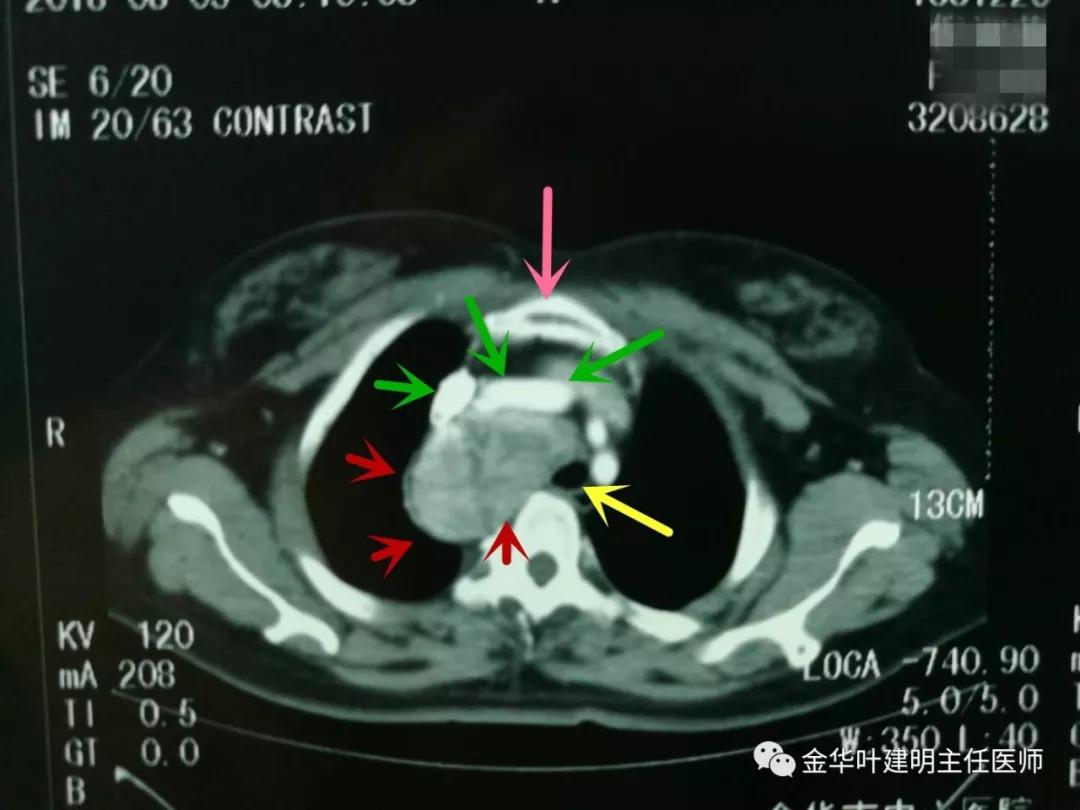

上图示胸部CT检查时扫到部分颈部,发现双侧甲状腺占位。红色箭头示甲状腺肿块,黄色箭头示中间的气管

上图示胸腔内的肿块自胸廓入口处就已经存在,极可能与甲状腺是相连的

上图红色箭头示胸腔内的巨大肿块,绿色箭头示无名静脉与上腔静脉,粉色箭头示胸骨,黄色箭头示受压移向左侧的气管,气管与肿瘤的后方是脊柱